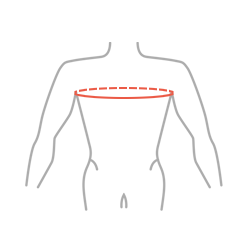

| Size | Chest circumference | How to measure |

|---|---|---|

| 1 | 40 – 50 cm |  |

| 2 | 50 – 60 cm | |

| 3 | 60 – 70 cm |

ATTENTION! To adjust the appropriate size, measure the chest circumference at the level of the armpits.